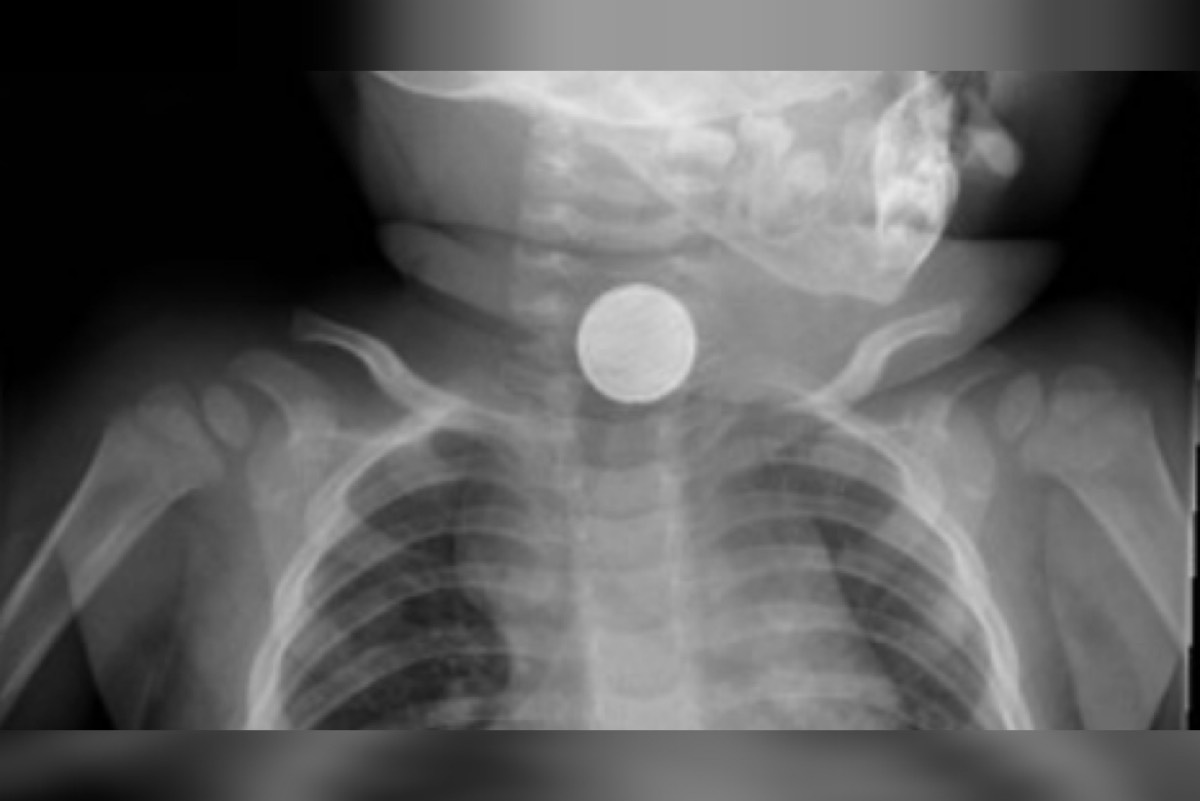

وقالت الصحة السعودية أن الطفل نقل لمستشفى بيشة للولادة والأطفال وهو يعاني من وجود جسم غريب في المريء أدى إلى صعوبة في البلع والتنفس. وبعد عمل الفحوصات السريرية والإشاعية تبيّن وجود بطارية محشورة بالمريء ليتم على الفور إدخاله لغرفة العمليات واستخراجها بالمنظار وبدقة عالية دون حدوث أي مضاعفات.

وأكد الفريق الطبي أن هذه العمليات تعمل بحذر شديد تحسباً لانفجار البطاريات داخل التجويف مما قد تتسبب بحدوث حروق كيميائية ومضاعفات مميتة